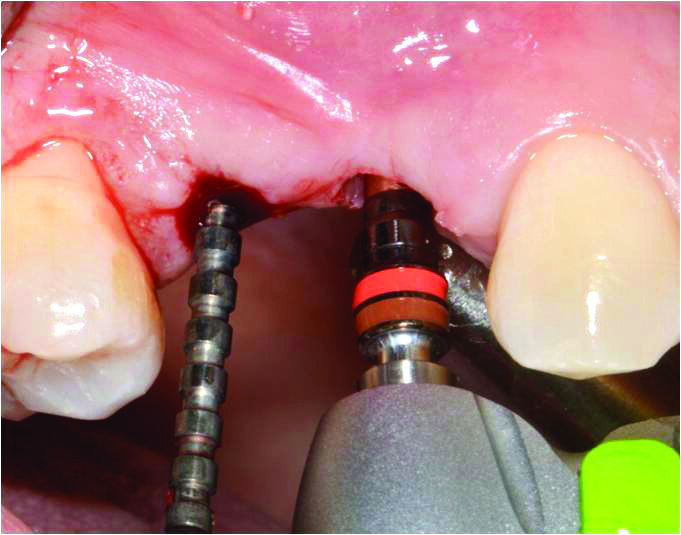

La preparazione dei siti implantari avviene mediante frese DNT2 (Alpha-Bio Tec, Israele) che dispongono di tacche di profondità evidenziate in contrasto cromatico e codici-colore per una migliore identificazione della profondità dell’osteotomia. Tali frese presentano tre scanalature e un’innovativa conformazione delle lame per praticare l’ostoetomia con precisione e massima stabilità nel taglio6. L’innovativo design delle frese DNT2 consente, inoltre, una ridotta produzione di calore durante la perforazione e l’alesatura del sito implantare (Fig. 5). La procedura osteotomica viene eseguita con tecnica flapless in modo da ridurre al minimo il riassorbimento vestibolare dell’osso crestale7 e la sintomatologia nel post-operatorio.

Fig. 5_Il pin di profondità guida la preparazione del sito del 14 con una leggera inclinazione distale della fresa per evitare di impattare la radice del 13.